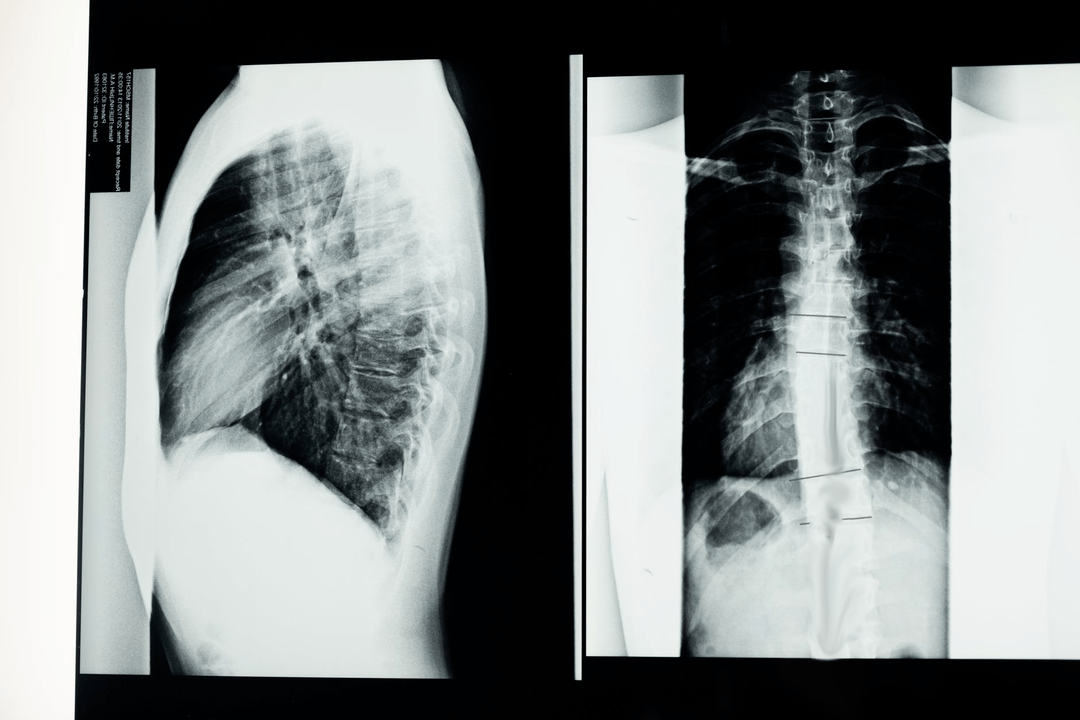

Pred začatím diagnostických štúdií neurológ zhromažďuje anamnézu pacienta a starostlivo študuje jeho sťažnosti. Osteochondróza má spoločné symptómy s niektorými inými ochoreniami, preto je dôležité vedieť rozlíšiť patológie. Röntgenové štúdie pomôžu potvrdiť diagnózu osteochondrózy: rádiografia, myelografia a počítačová tomografia.

Röntgenový prieskum vám umožňuje získať röntgenový obraz chrbtice alebo jej časti. Týmto spôsobom môže lekár určiť miesto postihnuté chorobou. Pre názornosť si vysvetlíme, ako sa dá osteochondróza určiť röntgenom: na snímke bude vidieť zúženie medzistavcovej platničky, prítomnosť kostných výrastkov (osteofytov) alebo zmenu tvaru segmentu chrbtice.